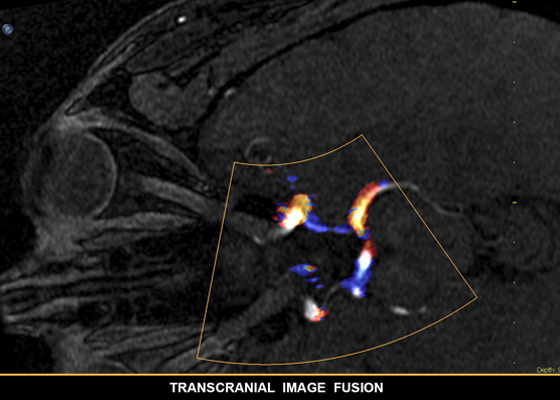

L’intelligence anatomique appliquée à l’échographie utilise la modélisation avancée des organes, la fonction de découpe des images et des outils de quantification éprouvés. Les examens sont ainsi plus faciles à réaliser, davantage reproductibles et plus riches en informations, ce qui permet de relever les défis cliniques et économiques des environnements médicaux actuels. L’intelligence anatomique est utilisée dans les solutions d’imagerie Philips telles qu’EchoNavigator, EP navigator et HeartNavigator. Aujourd’hui, elle fournit déjà aux cliniciens des outils de traitement sophistiqués mais faciles à utiliser. En outre, elle leur permet d’identifier rapidement et plus précisément une anatomie et des anomalies, d’évaluer le stade des maladies, de décider du traitement et de guider les interventions.

L’intelligence anatomique étudie les données échographiques d’un patient et applique une intelligence adaptative du système à l’aide de modèles anatomiques en 3D, pour obtenir plus facilement des résultats davantage reproductibles.